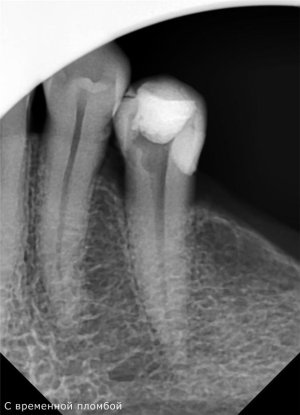

Здравствуйте! 21 апреля мне запломбировали каналы.Сутки зуб не болел,а вчера началась боль острая при надавливании.

Прошу специалистов внимательно разглядеть снимки.Мне кажется каналы,в корне не достаточно плотно запломбированы материалом и часть выходит за пределы корня.

Я делала через фотошоп контраст и увидела не заполненные места.